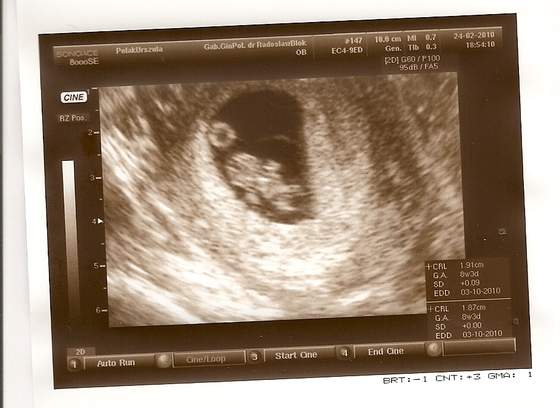

Jak to mój mąż wuefista stwierdził: widać już łapki i piłkę do ręcznej... :-)

Już ma prawie 2 cm... :tak:

Ulisia, a ta kropeczka nad dzidzią to co to ?

Niesamowite, jak przez dwa tygodnie te nasze dzidzie się zmieniają. :-D

A tak serio to ciałko żółte. Ono się podobno tym odżywia, czy jakoś tak.